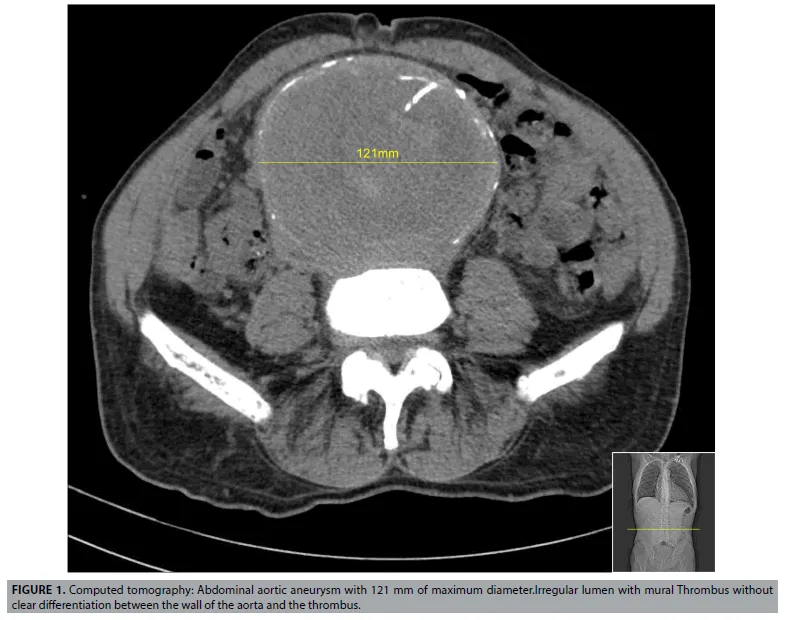

- Diagnosis: Ultrasound is best for screening/monitoring. CT with contrast for symptomatic patients or pre-op planning.